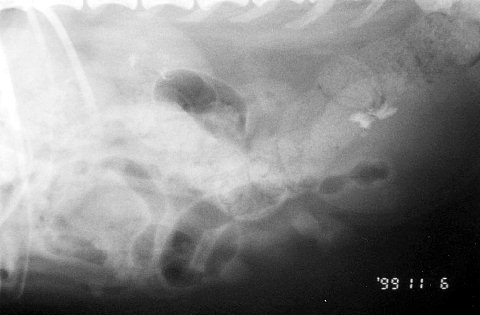

まずは膀胱結石です。

この写真では日付のところをず〜と上にいくと丸い臓器があります。

それが膀胱で、その中に石があります。

この症例では腎臓にも結石がありますね。

これは小さい結石がたくさんあります。